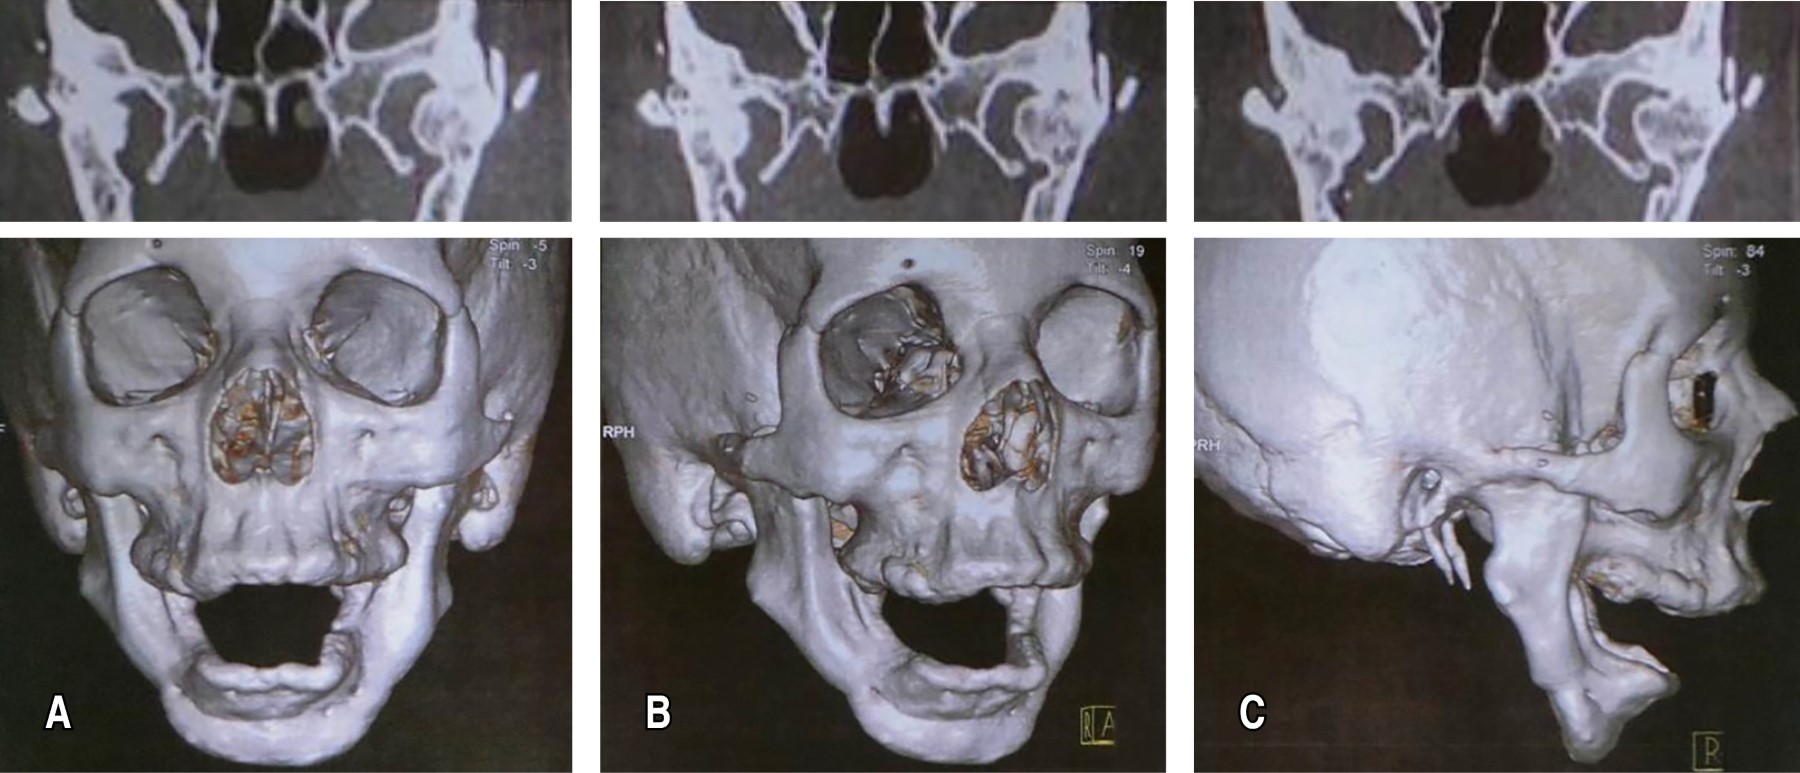

Finalmente, se realizó una tercera cirugía, únicamente con avance del mentón, con el objetivo de aumentar el espacio de la vía aérea. Sin embargo, incluso después de los tratamientos realizados, la paciente seguía presentando mialgia, anquilosis total de la ATM, apnea grave y problemas dentales severos, habiendo perdido todos los dientes debido a la dificultad para realizar una adecuada higiene bucal (Figura 1).

Figura 1